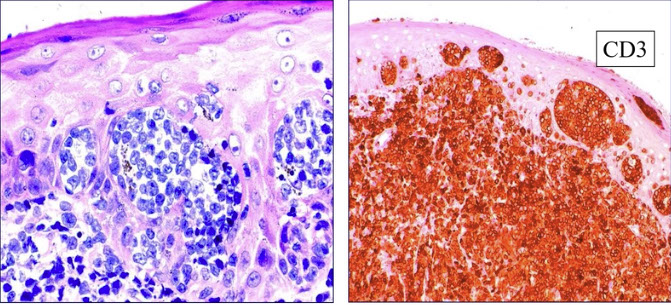

Cutaneous lymphoid hyperplasia in a 72-year-old man who presented with several purple-brown plaques on his cheeks and temples. A, The nodular infiltrate extends through the dermis with sparring of the overlying epidermis. B, It is characterized by scattered follicles with well-defined, reactive-appearing germinal centers, some of which have surrounding mantle zones. Many CD20-positive B cells are in the reactive follicles (C), and more numerous CD3-positive small T cells are present in the interfollicular areas (D). B-cell clonality studies (not shown) were negative for a clonal IGH or IGK gene rearrangement. [19]